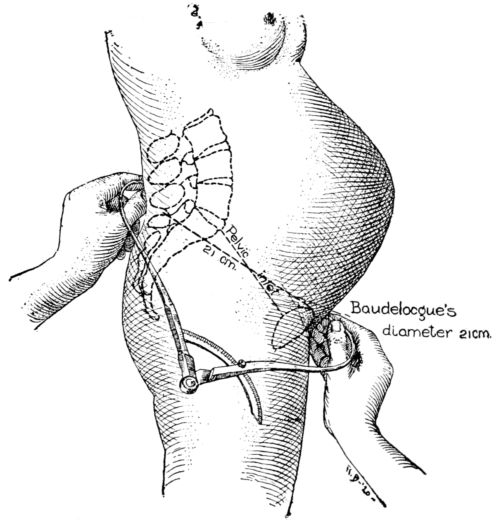

| 7. | Diagram showing method of measuring Baudelocque’s diameter | 27 |

Baudelocque’s diameter is the third measurement and is taken with the patient lying on her side. (Fig. 7.) It is the distance from the top of the symphysis to a depression just below the last lumbar vertebra. This depression is easily located as it also marks the upper angle of a space just above the buttocks, which in normal pelves is quadrilateral. In malformed pelves this quadrangle may be so misshapen as to become almost a triangle with the apex directed either up or down. This dimension 26is sometimes called the external conjugate and ordinarily measures 21 centimetres.